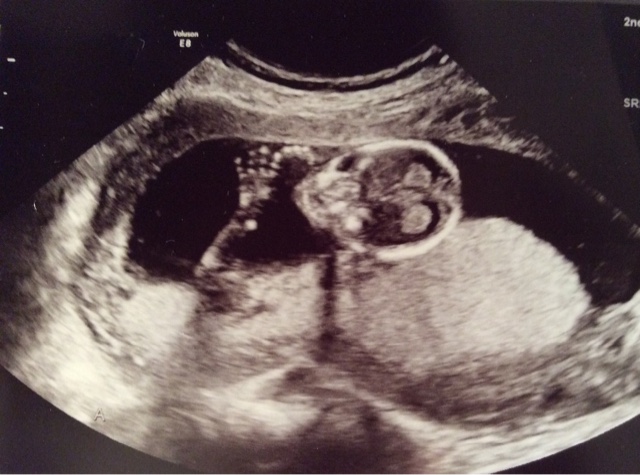

The only slight concern was that Baby B's placenta is low lying, which might explain why I had some bleeding the other week. Hopefully it moves upward as my uterus grows. I really don't want to have to worry about another reason why I could lose these babies. So for now per doctors orders Matt and I can no longer have "relations" as he calls it. My doctor chuckled when he told us this and told Matt that he was going to have to take a lot of cold showers. Oh well... What's another 5 months without it... Right?

How Far Along: 18 weeks

Gender: still unknown... Well kind of.